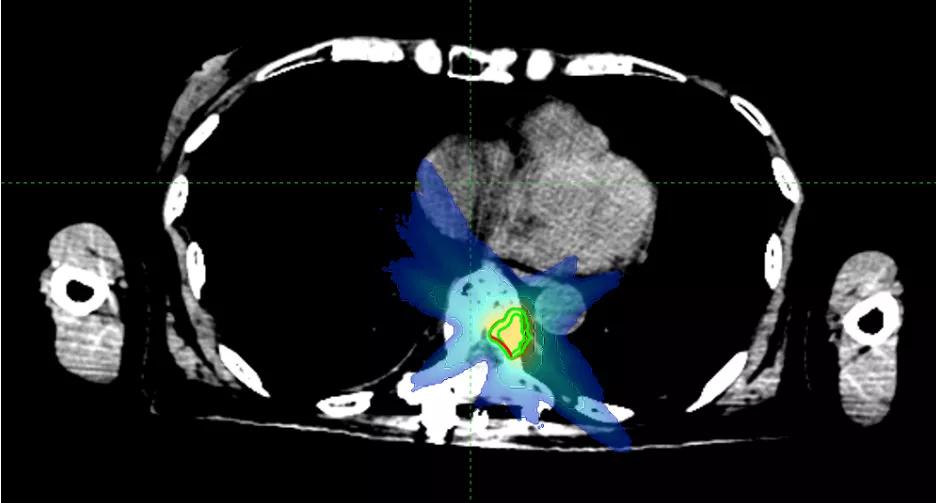

乳腺癌脊柱骨转移,病灶离脊髓很近,射波刀为她开了一扇希望之窗

66岁的罗女士,2019年6月进行左乳腺切除,术后病理报告为浸润性导管癌,三阴性,2019年7月开始为期6周期的化疗。

2021年3月检查发现,T7椎体及T9椎体左侧椎弓根骨质破坏伴FDG代谢增高,考虑骨转移,伴T7椎体病理性骨折。同月做了胸椎融合术+脊柱肿瘤切除人工椎体置换术。2021年4月开始,化疗4周期。2021年9月检查发现,T9-11转移性肿瘤较前增大。

据罗女士的主管医师周霞副主任医师介绍,因T9病灶靠近脊髓附近,如果常规放疗,很可能会造成脊髓不可逆的损伤。于是慕名来到国科大肿瘤医院,胸部放疗科周霞副主任医师为她量身制定了放疗计划,近期开始进行射波刀放射治疗。

周霞介绍,脊柱骨转移瘤是射波刀的拿手好戏。脊髓往往对近在咫尺的脊柱骨转移瘤避无可避,而精准的照射在给它温柔的保护之余,高剂量射线痛击骨内病灶,可以达到缓解疼痛、控制肿瘤的目的。

PGTV1(T9)

PGTV2(T11)